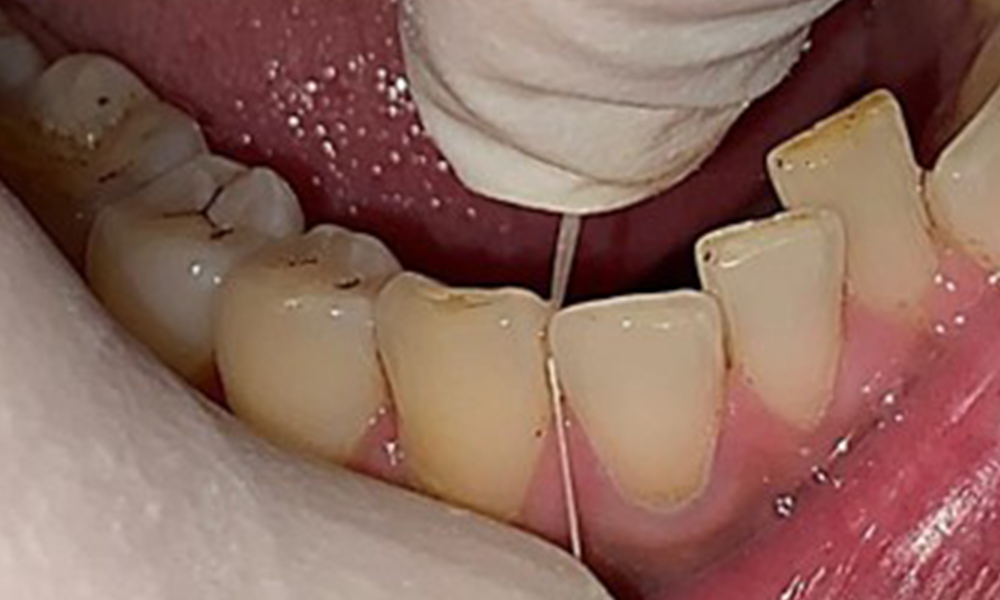

Dental findings

The patient has full dentition with a total of 28 teeth. There were noteworthy erosions and attritions. (Fig. 4, Fig. 5). Due to bruxism, the patient has been wearing a splint with an adjusted bite block at night for many years. The erosions were caused by long-term consumption of isotonic beverages. No periodontal bone loss or active caries were observed.

Close-up view of teeth

Fig. 5: Close-up view of teeth 45 to 47. The green arrows show dental attrition and erosions of the buccal cusps with partial enamel loss, © Dr R. Krapf